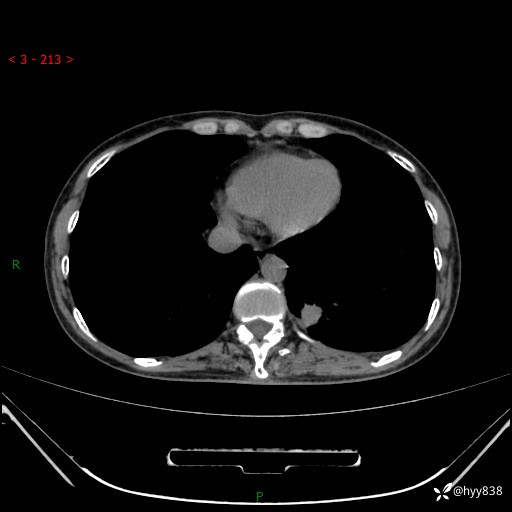

增强动脉期+静脉期

各期CT值:48hu 65hu 76hu